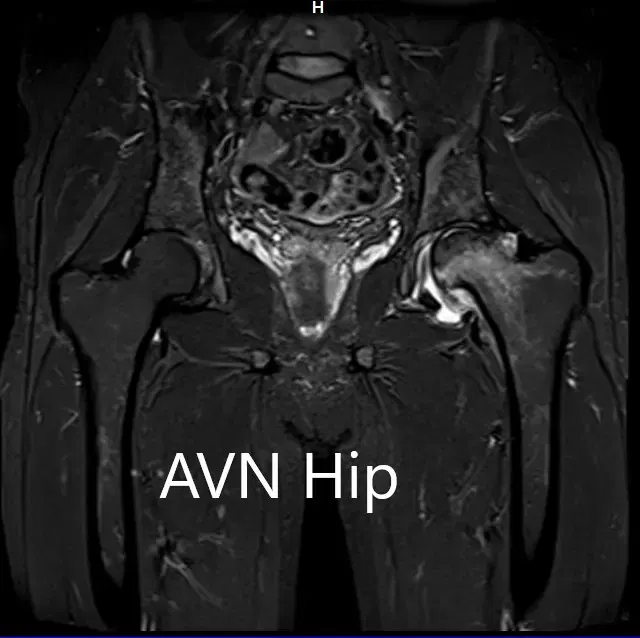

Se realizó una resonancia magnética para confirmar el diagnóstico y la estadificación de la enfermedad. La cabeza femoral izquierda estaba colapsada con contorno irregular y mostraba áreas de intensidad de señal alterada con una línea de demarcación. Zonas hipointensas tanto en T1WI como T2WI observadas en la cabeza sugestivas de esclerosis. Se observó edema de médula circundante

La cadera izquierda presentaba necrosis avascular avanzada con colapso. La cadera derecha no estaba afectada en ese momento. Recibió formación sobre el agravamiento del colapso de la articulación de la cadera que provocaba sus síntomas. Aunque el paciente era joven, se le recomendó una cirugía de reemplazo total de cadera debido al colapso de la cabeza del fémur por artritis.